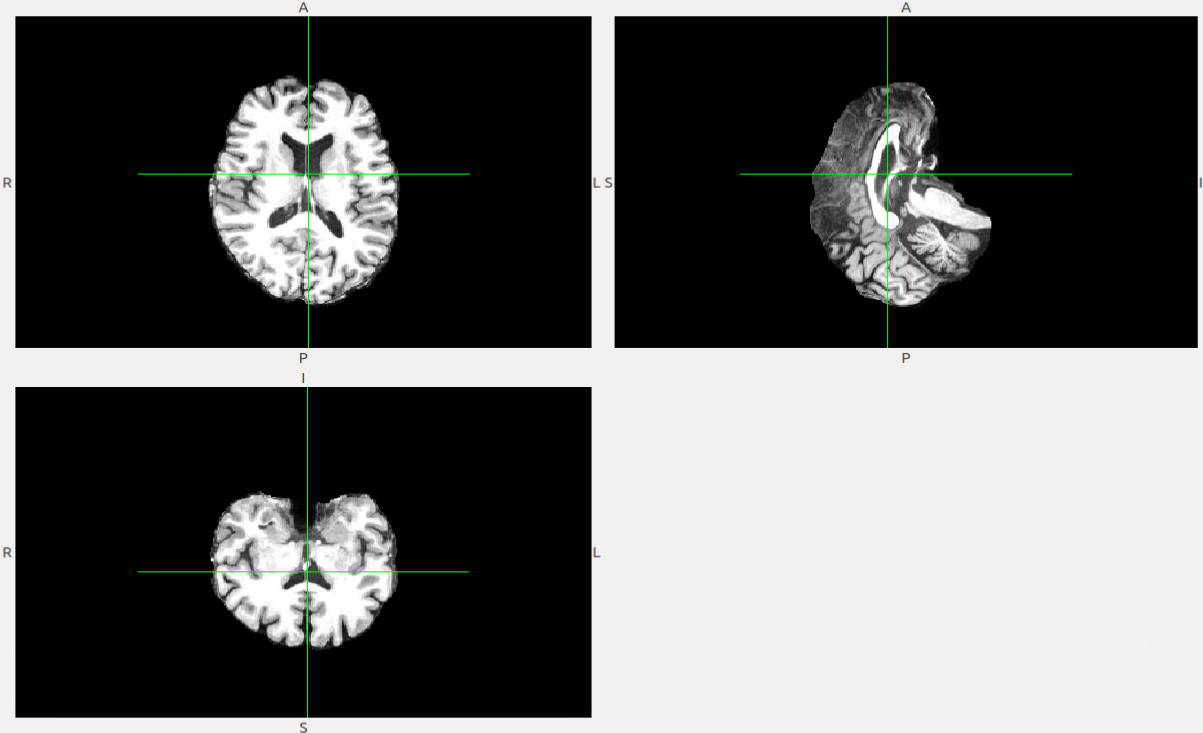

In this section, we present the experimental results of the different steps of the proposed CAD system to diagnose PD is presented. First, using FreeSurfer, the preprocessing step prepares the MRI data for the next steps. Fig.3 shows the MRI for subject 310231023102 and the resulting image after preprocessing.

Refer to caption

(a) Original MR image.

(b) Preprocessed MR image.

Figure 3: Preprocessing results for one of the subjects.